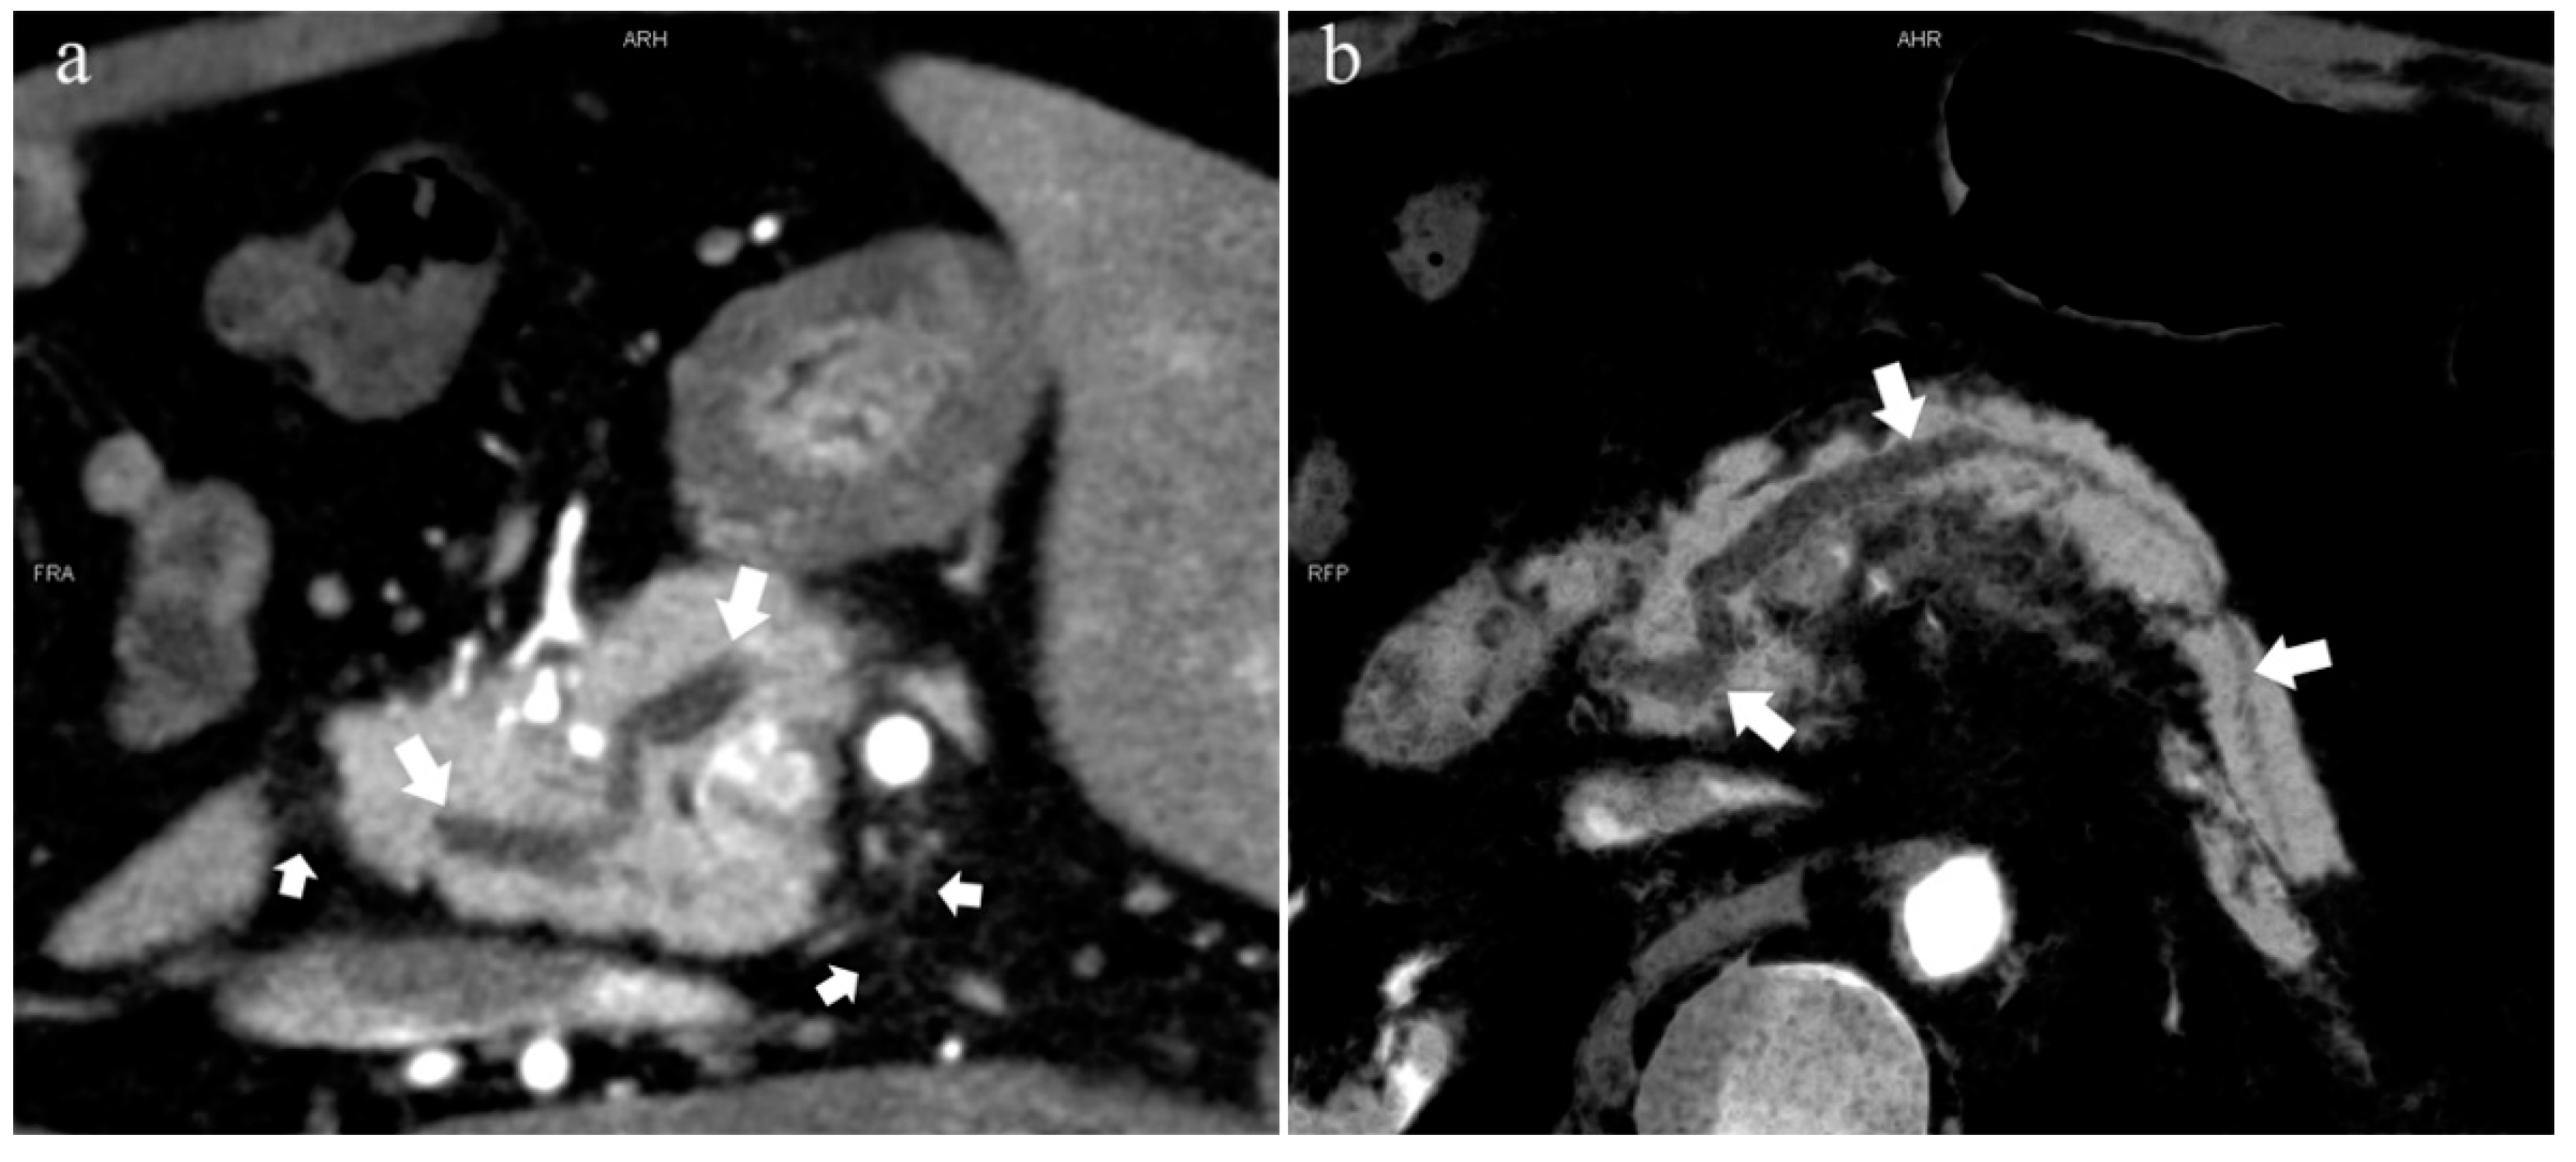

5.2. Special Types of Pancreatic Duct Variation

5.2.1. Pancreas Divisum (Type 4)

5.2.2. Ansa Pancreatica